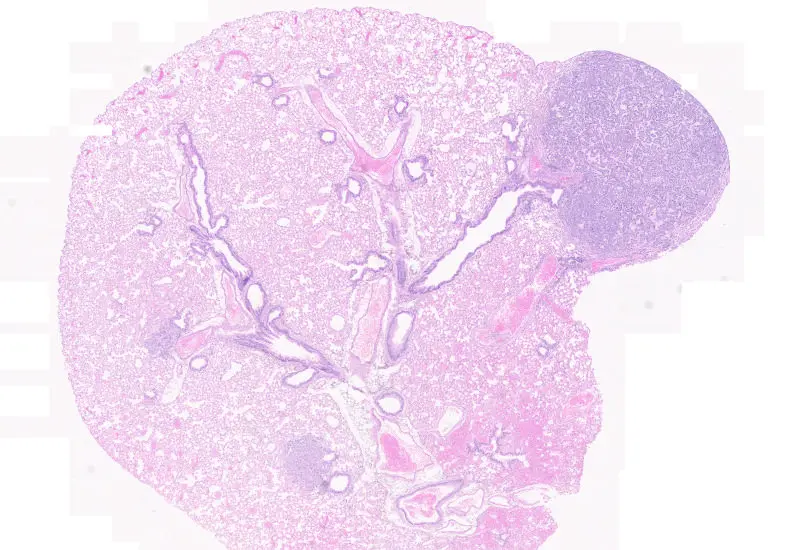

The Tumor Foci App allows to detect the whole tissue and more important tumor foci based on nuclear structure analysis, mainly on HE staining. The number and area of tumor foci as well as their density is measured.

Original image

Tumor foci detection